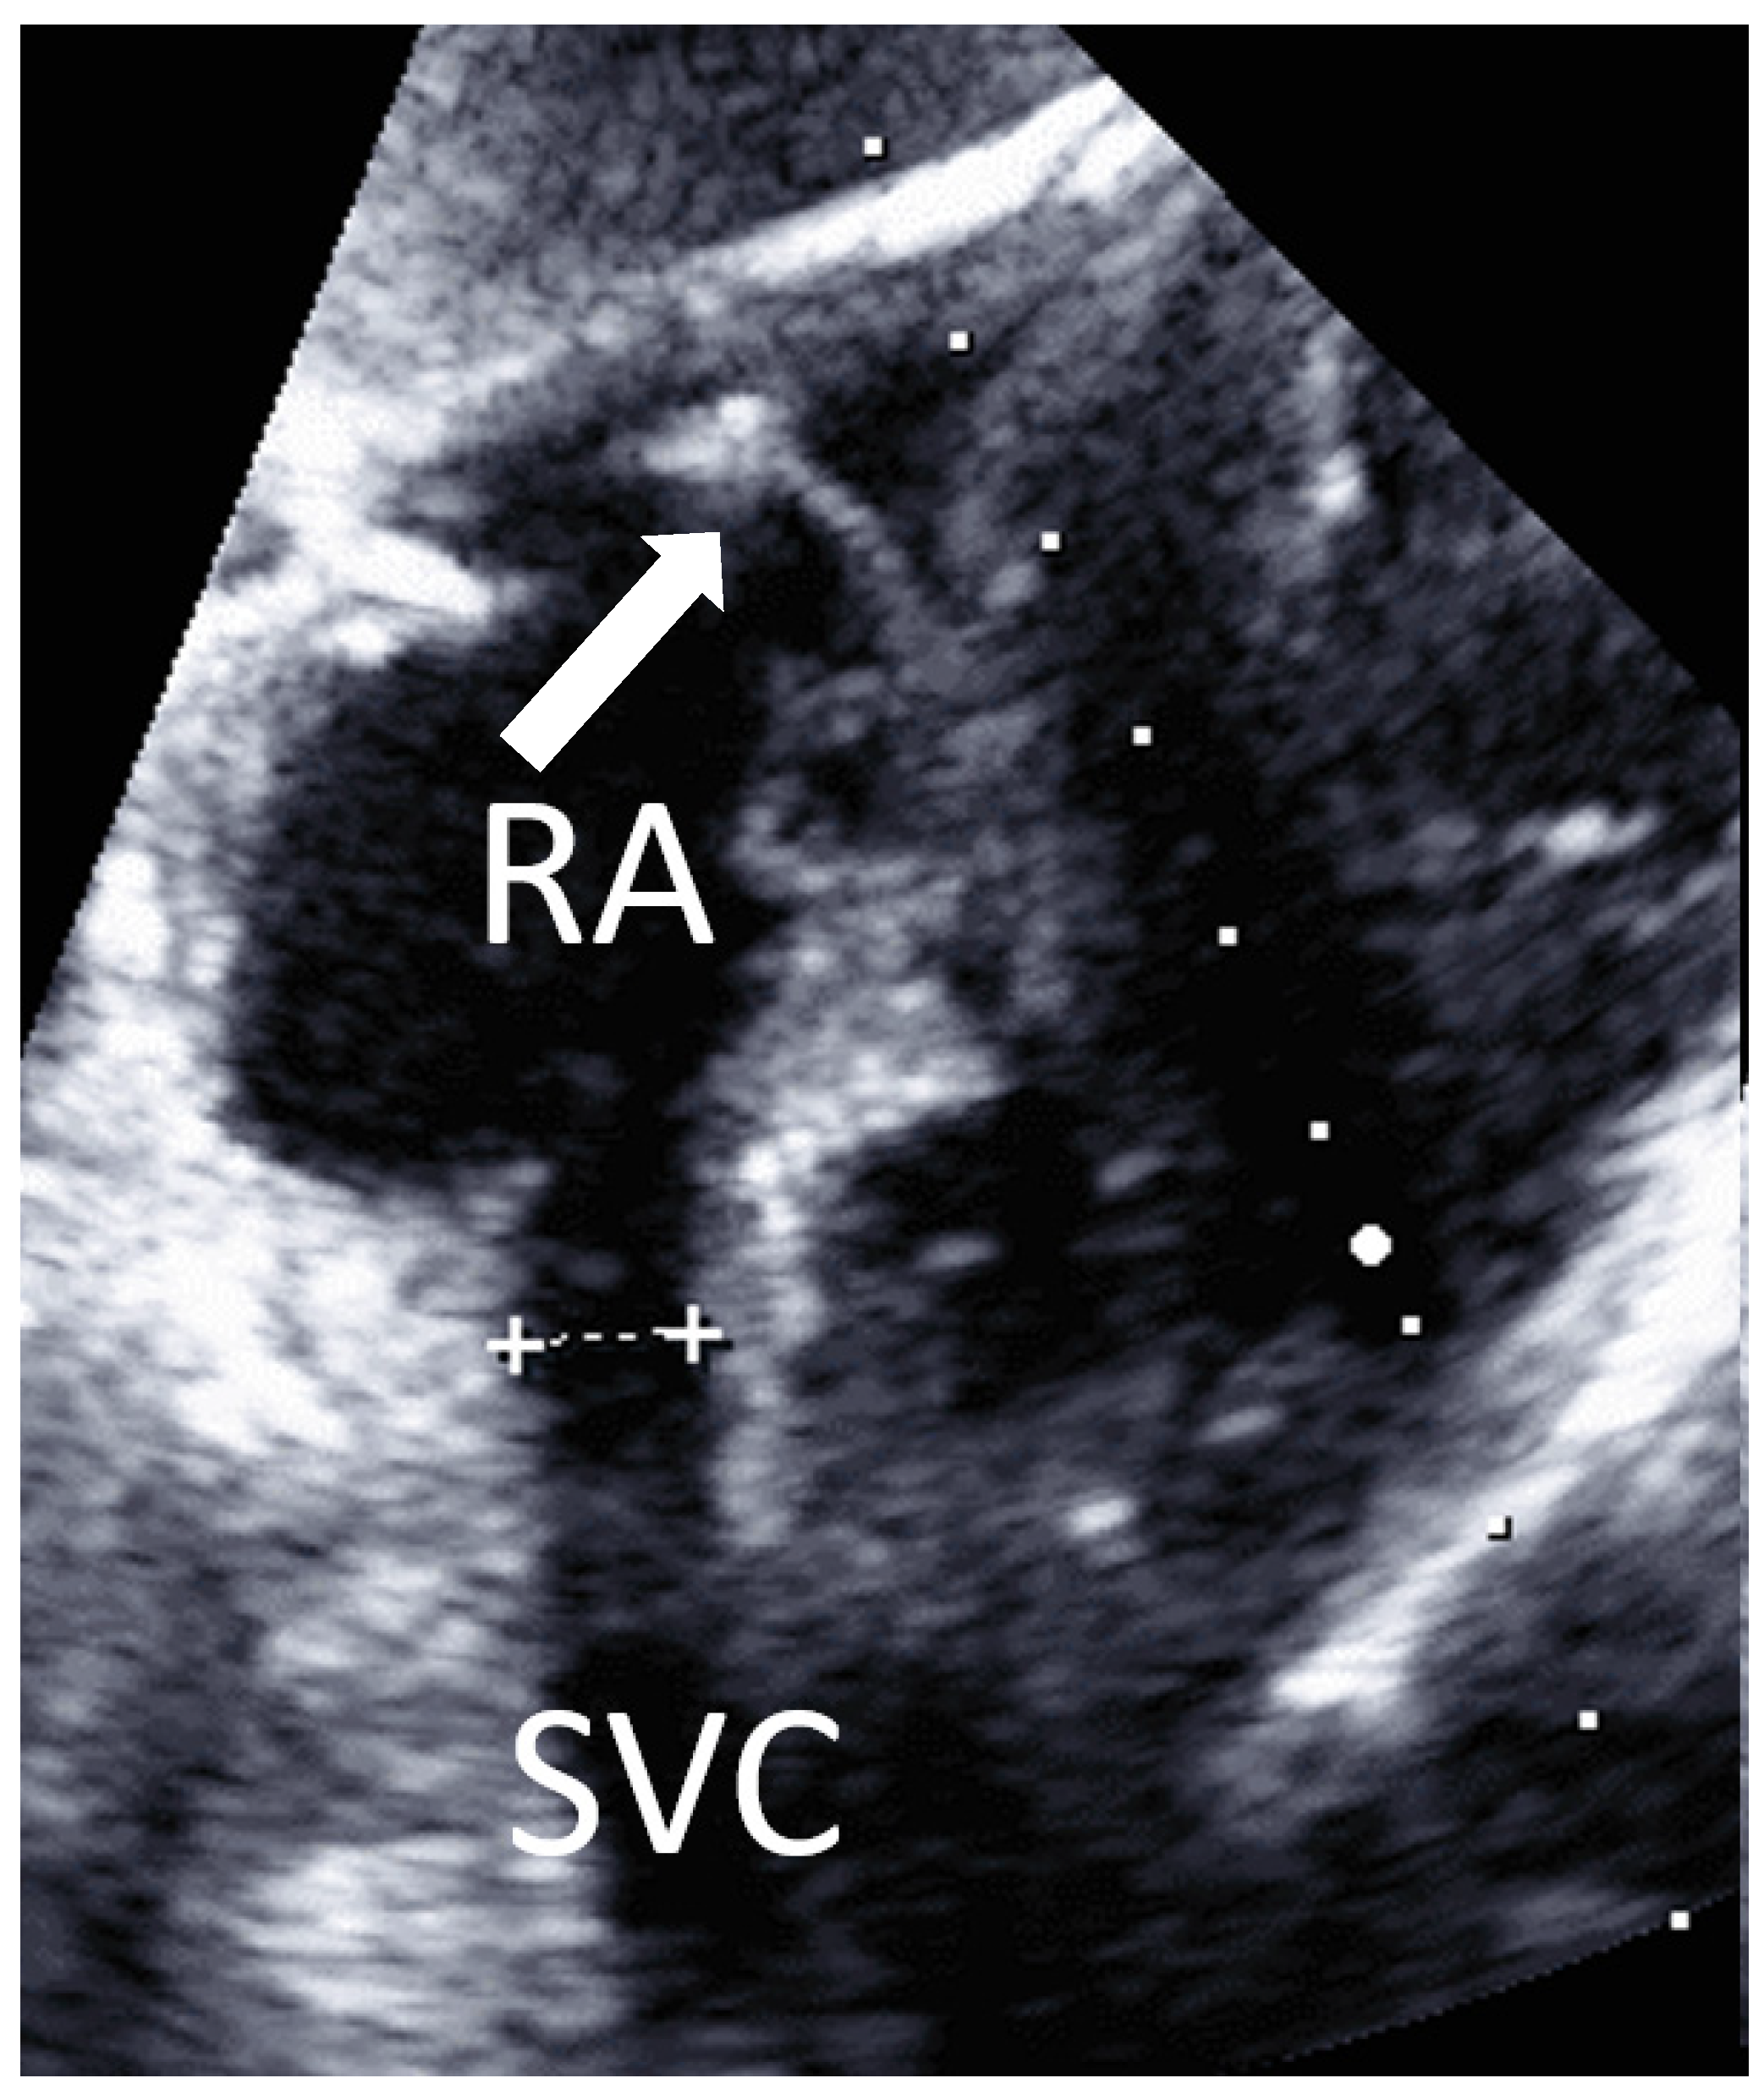

• Fourth: subcostal view

A cardiac sector transducer was primarily used. The use of a linear transducer/hockey stick might also be possible in young children. The limiting factor is the penetration depth of the linear transducer or hockey stick.

View from subcostal, a four-chamber view can be seen. By tilting the transducer, the superior vena cava is displayed in a longitudinal section, and the entry of the superior vena cava into the right atrium is clearly visible (Figure 5). A PW Doppler signal can be placed in the confluence of the superior vena cava to the atrium and a vena cava flow signal can be detected.

Figure 5. Subcostal view: superior vena cava (SVC) and right atrium (RA). Arrow: J-wire in RA. Caliper indicates SVC diameter.